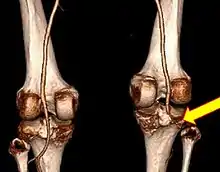

Knee dislocation

A knee dislocation is an injury in which there is disruption of the knee joint between the tibia and the femur.[3][4] Symptoms include pain and instability of the knee.[2] Complications may include injury to an artery, most commonly the popliteal artery behind the knee, or compartment syndrome.[3][4][7]

They may be divided into five types: anterior, posterior, lateral, medial, and rotatory.[4] This classification is based on the movement of the tibia with respect to the femur.[11] Anterior dislocations, followed by posterior, are the most common.[2] They may also be classified on the basis of which ligaments are injured.[2]